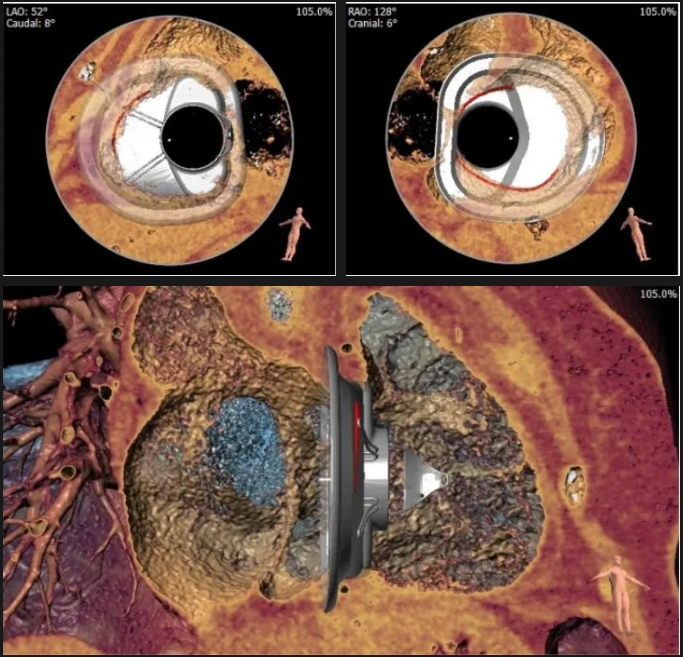

術(shù)后三維超聲

術(shù)后即刻經(jīng)食道超聲可見,三尖瓣假體瓣膜位置合適,牛心包瓣葉運(yùn)動狀態(tài)良好,開閉正常,瓣周及瓣葉對合緣處未見明顯返流,心電圖及心包狀態(tài)較術(shù)前無明顯變化。

術(shù)前術(shù)后返流情況對比